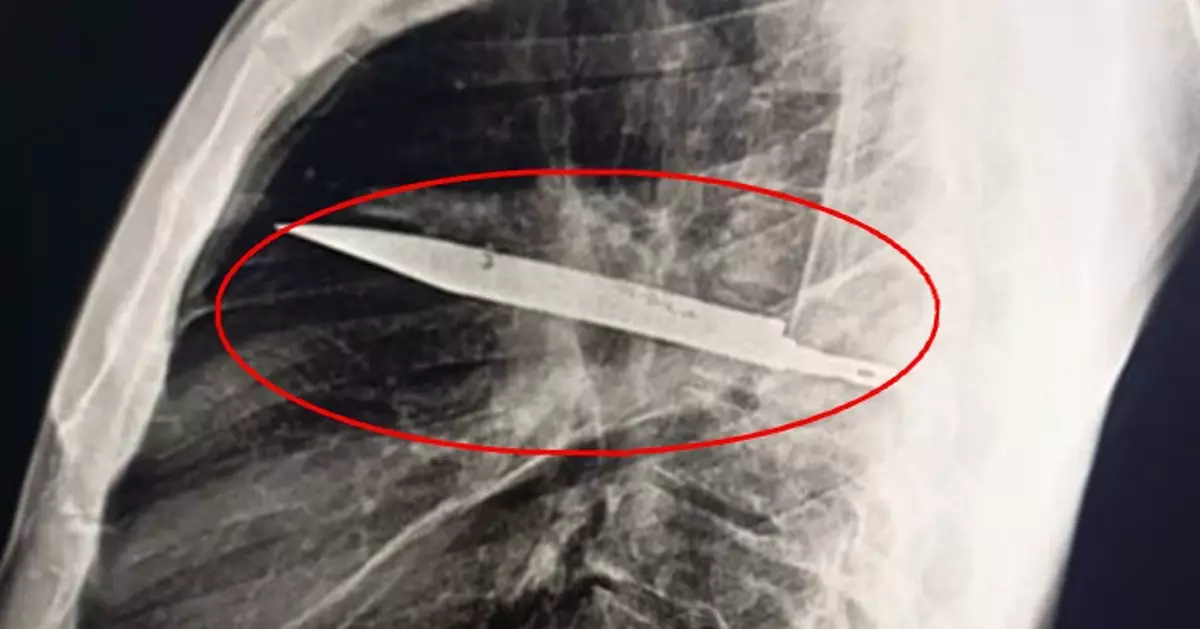

胸部X光檢查揭開謎底,影像清楚顯示有一把刀埋在患者胸腔內,神奇的是這把刀從右肩胛骨刺入,奇蹟般避開所有重要器官。

坦桑尼亞44歲男乳頭痛流膿,醫生檢查驚揭胸腔插刀8年。圖片來源:外科病例報告期刊